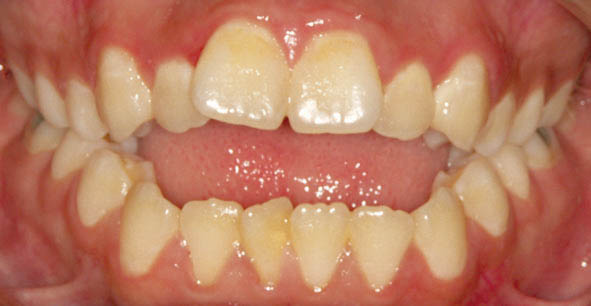

شکل 38-3

شکل 39-3

شکل 40-3

شکل 38-3 الی 40-3: اپن بایت شدید